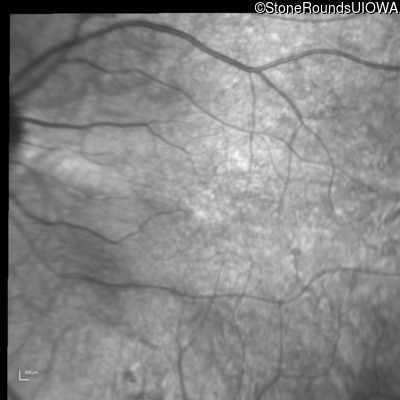

Infrared Fundus Photograph - Left - 20/40 -2

Exemplar